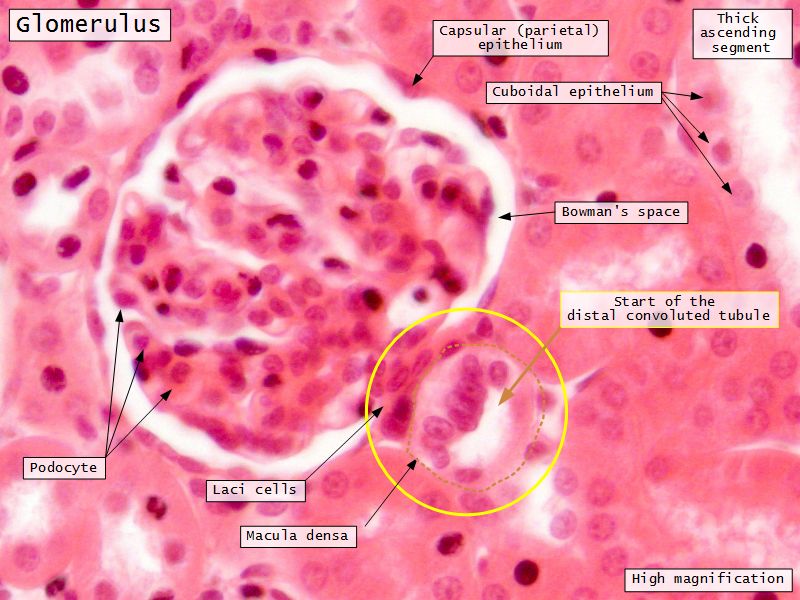

Renal corpuscle

- Tuft of capillaries

- grow into

- Blind end of nephron

- Several layers of epithelium

- Two sides

- Vascular pole

- Tubular pole

Epithelium layers

- Capillary endothelium

- Visceral layer of epithelium

- Podocytes

- Resting on glomerular basement membrane

- Capsular space

- Parietal layer of epithelium

- Simple squamous epithelium

Juxtaglomerular complex

Area where distal convoluted tubule return to glomerulus and pass through the notch between the afferent and efferent arterioles. Modification of the wall of the tubule and afferent arteriole and presence of specialised cells in the connective tissue.Modifications

- Distal convoluted tubule

- Macula densa

- Narrow epithelial cells

- Nuclei densely packed

- CT cells

- Laci cells

- Similar to mesangial cells

- Afferent arteriole

- Modified smooth muscle cells

- Juxtaglomerular cells

- Secretory function